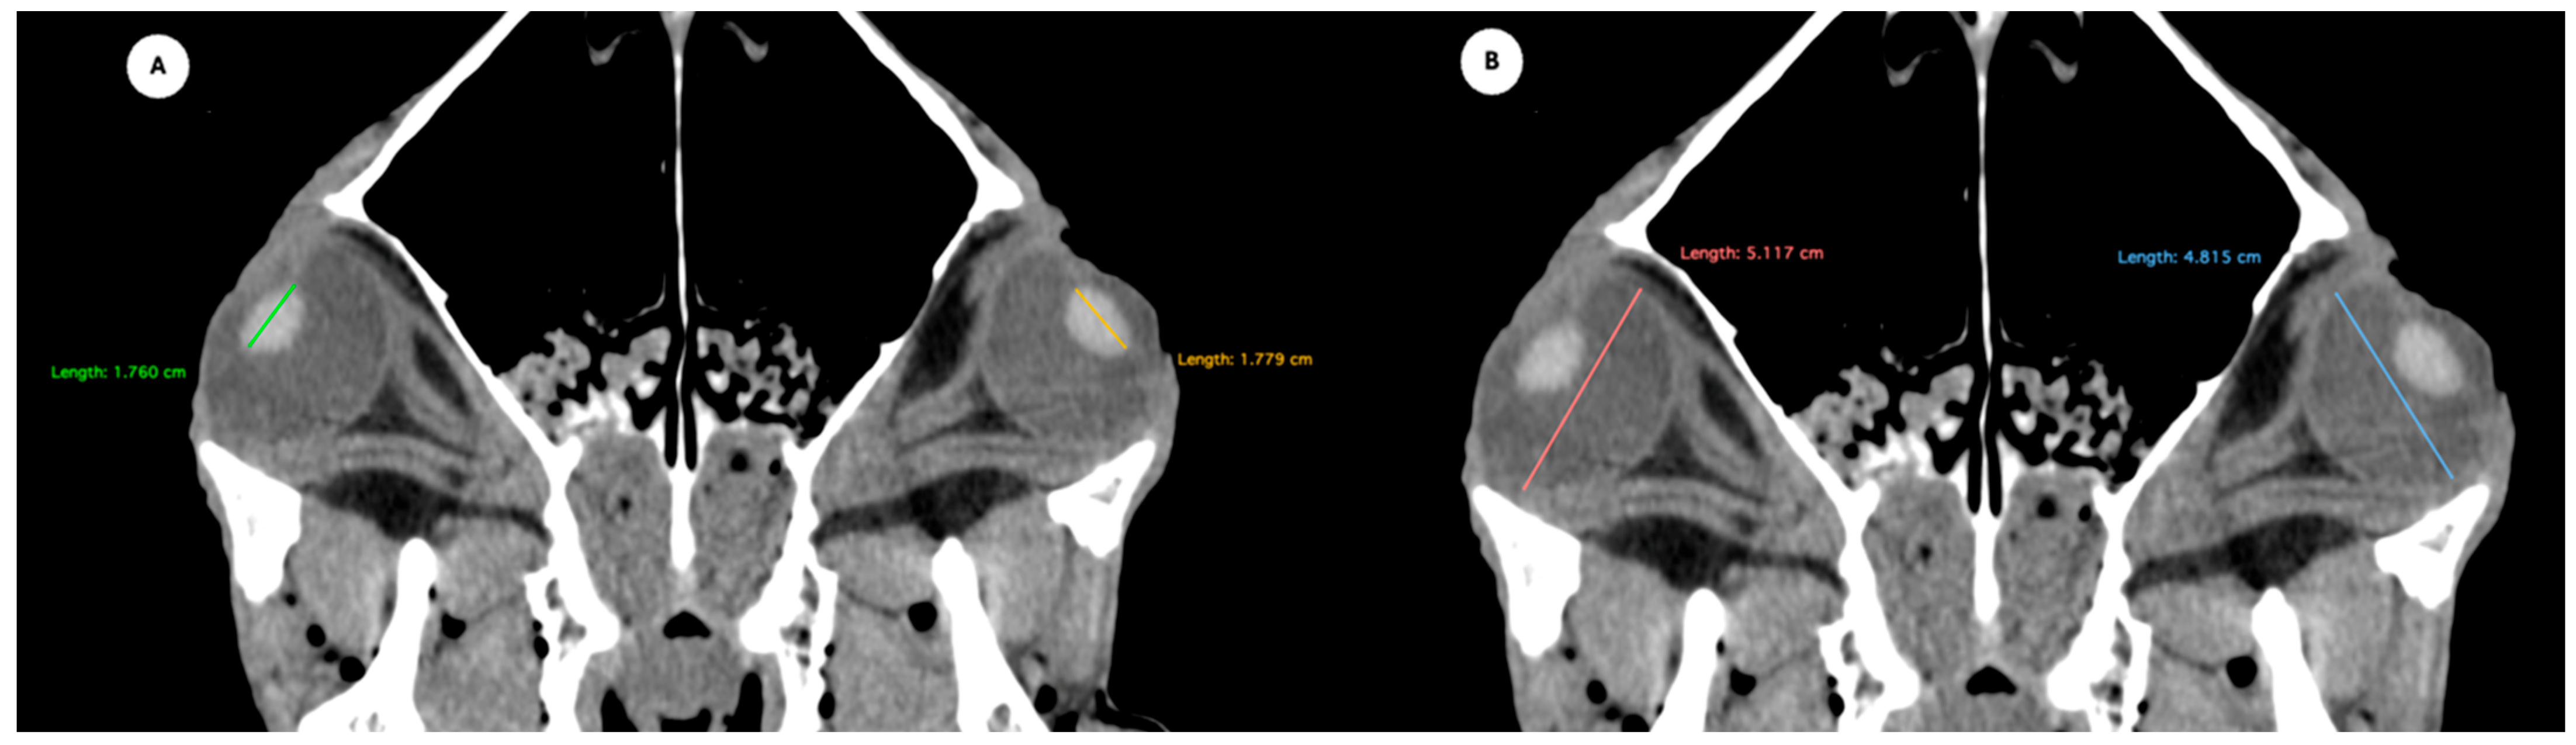

Figure 1. (A) Transverse multiplanar reconstruction (MPR) of the equine eyeball showing the maximum anterior–posterior distance (axial length), measured from the external surface of the cornea to the internal surface of choroid/retina/sclera, and the maximum latero-medial distance (equatorial width), measured perpendicular to the axial length. (B) Transverse MPR illustrating lens dimensions, with the latero-medial distance (equatorial width), measured at its widest point.

Figure 2. Dorsal multiplanar reconstruction (MPR) images showing (A) the maximal latero-medial distance of the lens and (B) the maximal latero-medial distance of the eyeball, measured perpendicular to the axial length, immediately caudal to the lens. - Orbital cavity height: Maximal dorsoventral distance of the orbital cavity at the level of the eyeball.

Table 1 provides summary statistics (mean, median, range, and standard deviation) for the internal ocular measurements of the left eye, right eye, and both eyes combined across all 20 horses. The average ocular measurements indicated that the eyeball height (5.19 ± 0.13 cm) was greater than its width (4.28 ± 0.12 cm), confirming the characteristic oval shape of the equine eye. The mean axial length was 5.09 ± 0.17 cm, consistent with previous descriptions of large-globe morphology in horses. The orbital cavity measured 5.27 ± 0.12 cm in height and 6.29 ± 0.14 cm in length. The anterior and posterior chambers had mean widths of 0.56 ± 0.07 cm and 2.26 ± 0.09 cm, respectively. The lens exhibited a mean height of 1.53 ± 0.06 cm, width of 1.23 ± 0.06 cm, and length of 1.63 ± 0.04 cm. These results collectively reflect the regular proportions and bilateral symmetry of the equine eyeball and its internal structures, as detailed in Table 1. The Mann–Whitney U test revealed no statistically significant differences in the measurements between the right and left eyes. Similarly, when all variables were considered collectively, the analysis confirmed the absence of significant differences between both eyes